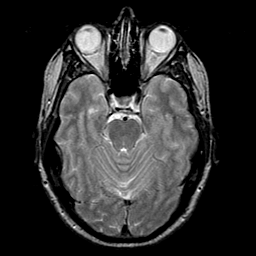

glioma overlay -- Slice #9

[Home][Help][Clinical] Slice 9